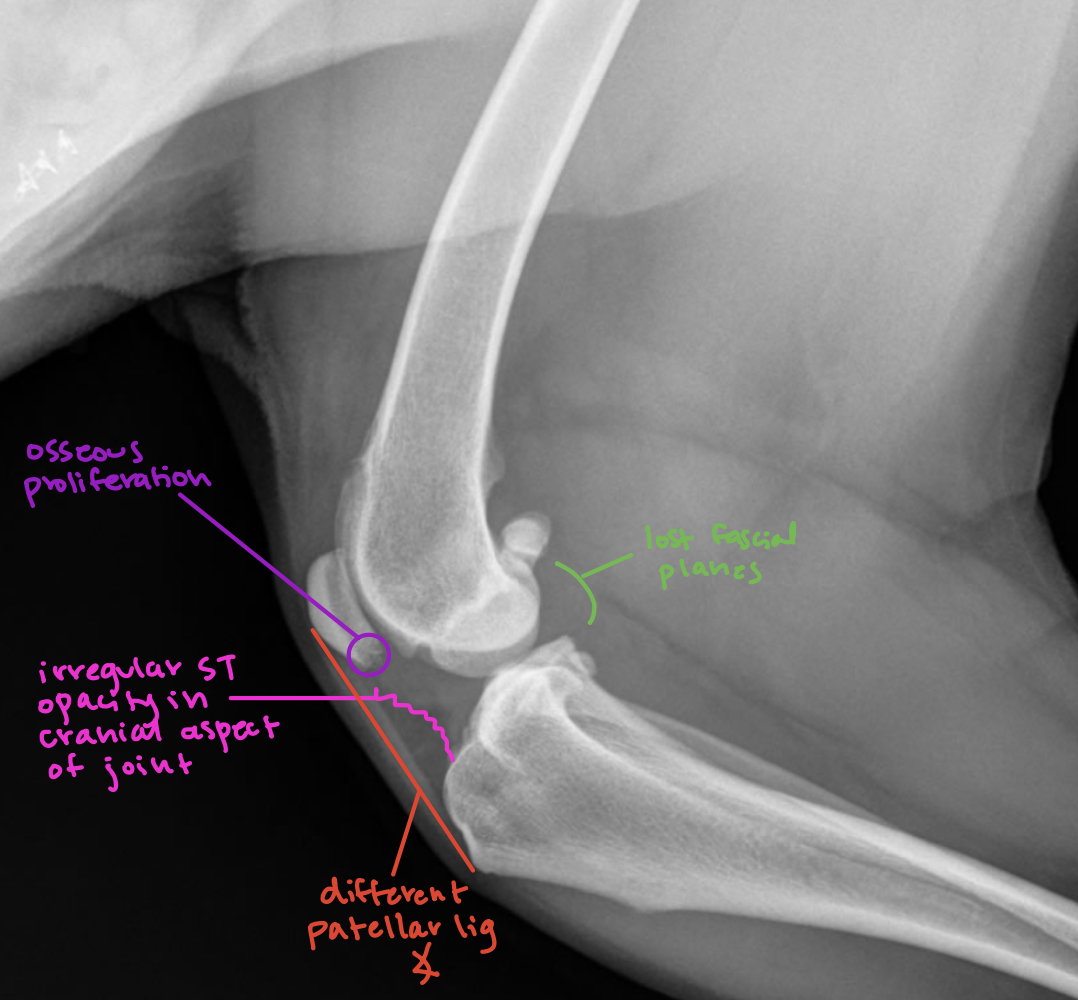

What pathology is going on here?

A

purple: osseous proliferation

red: patellar ligament angle change

pink: soft tissue opacity increase - cranial aspect of joint

green: lost fascial planes